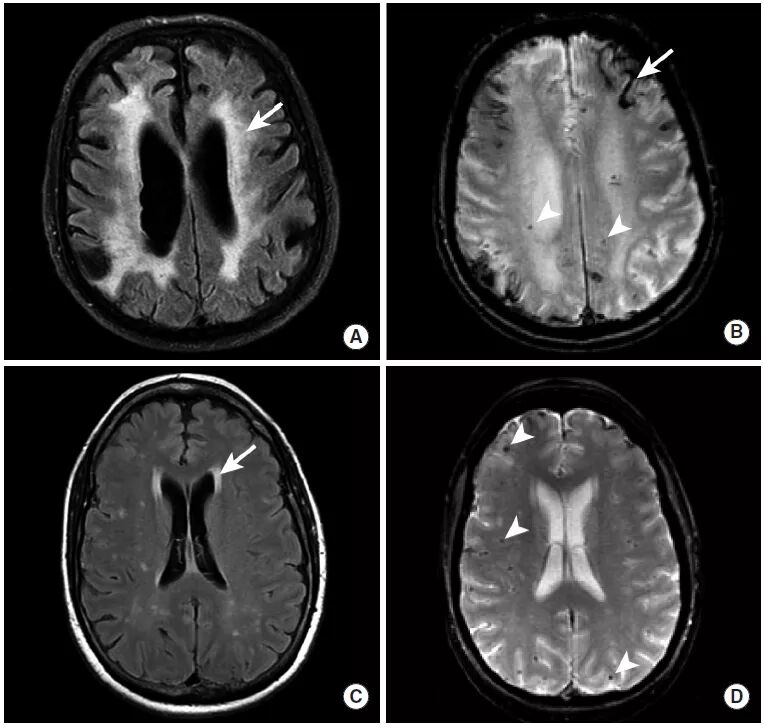

图9

本图显示了两名脑淀粉样血管病患者的一系列MRI检查序列。

图A、B:本例患者的MRI的FLAIR序列中,整个脑白质区域表现出了弥漫性的高信号异常,即继发于动脉壁中淀粉状蛋白-β肽沉积的微血管病变(图A,长尾箭头)。此外,皮层出血(图B,长尾箭头)和微出血灶(图B,三角箭头)显示为异常低信号。

图C、D:第二例患者的影像学检查中,脑白质异常不如前一例显著(图C,长尾箭头),但仍然存在数个微出血灶(图D,三角箭头)。